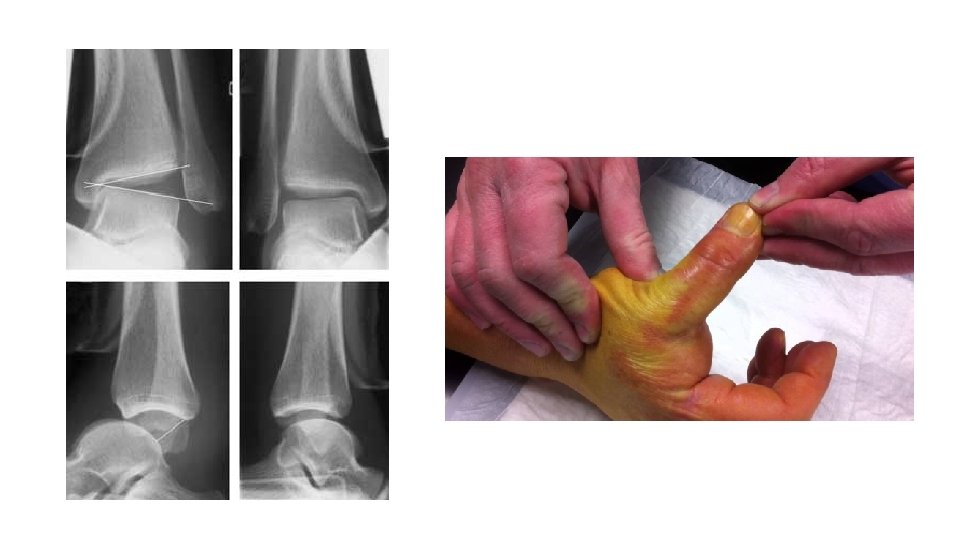

• Epaule • Coude • Patella • Hanche et PTH • Doigts •

• Epaule • Coude • Patella • Hanche et PTH • Doigts • Mâchoire • Tendon d’Achille

• Syndactylie • Immobilisation intrinsèque plus